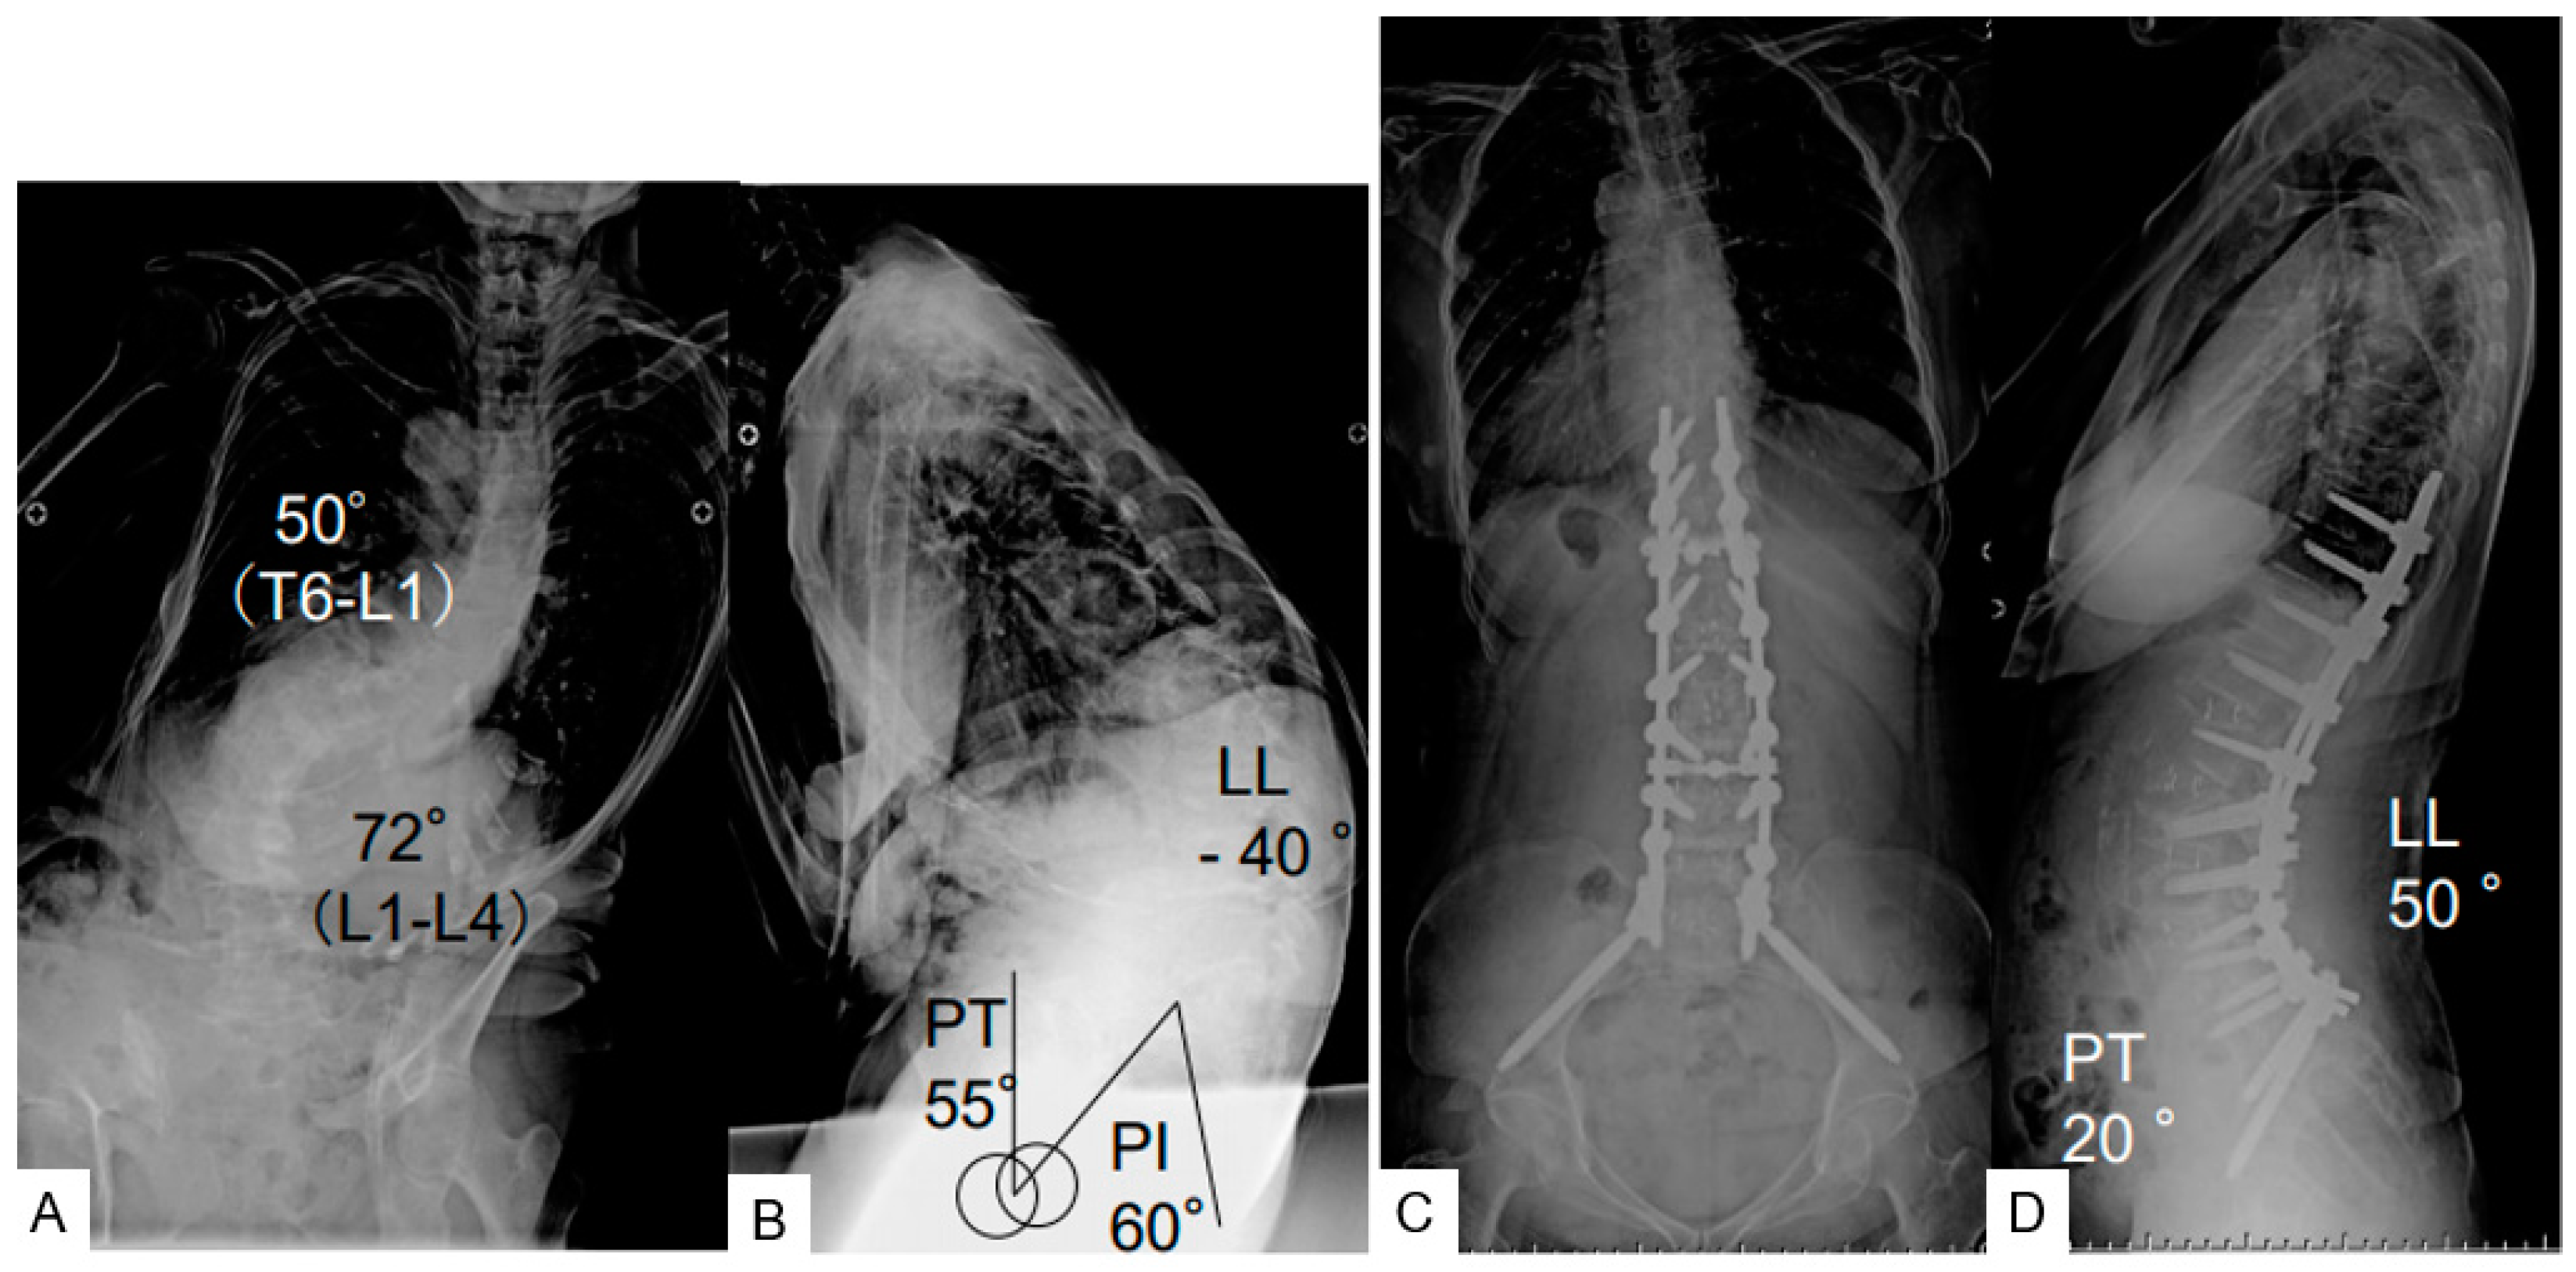

The study was approved by our institutional review board (No.287). We have obtained fully informed consent from the patients for this study. From June 2017 to August 2019, 25 female patients with ASD who underwent corrective surgery at our hospital were included in the study (Table 1, Figure 1). Inclusion criteria for this study were patients aged 60 years or older with the presence of at least one of the following: the sagittal vertical axis (SVA) 95 mm or more, pelvic tilt (PT) 30 degrees or greater, and/or coronal Cobb angle 30 degrees or greater [4]. Exclusion criteria were spinal deformities resulting from neuromuscular disease, spinal infection, or tumor. The surgeries were performed in the two stages, first OLIF L1 to L5 (or S1), secondly posterior corrective fusion basically from T10 to pelvis. We also evaluated hospital stay, % home return, open/MIS surgery, upper instrumented vertebra (UIV), and complications. BMI: Body mass index.

Figure 1.

A 79 female, adult spinal deformity, (A): preoperative posteroanterior radiogram, (B): preoperative lateral radiogram, PI 60°, PT 55°, LL −44°, SVA 150 mm, PI-LL 100°, (C): postoperative posteroanterior radiogram, PI 60°, PT 20°, LL 50°, SVA −15 mm, PI-LL 10°, (D): postoperative lateral radiogram.